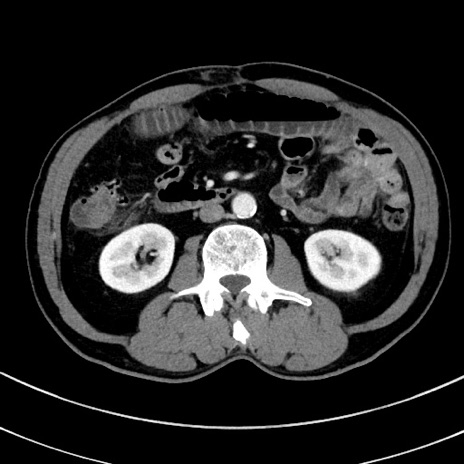

冠状断像

【症例】 60歳代男性

【主訴】 黒色吐物

【現病歴】 4日前から嘔気自覚、2日前の朝食後にも嘔気あり、自分で手で嘔吐反射起こし嘔吐したところ血が混ざっていたため受診。

【既往歴】 5年前汎発性腹膜炎を伴う急性虫垂炎で手術、高血圧、前立腺肥大症、高脂血症

【身体所見】 腹部正中に手術癩痕あり 腹部平坦・軟圧痛なし膨満感あり

【データ】WBC 8400、CRP 4.54